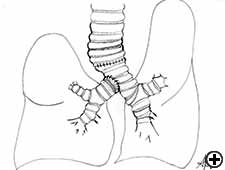

In isolated carinal resection and reconstruction, applicable for centrally located, low grade and small tumors (Video 8), the right and left main bronchi can be medially sutured to create a new carina, that is subsequently anastomosed to the distal trachea (Figure 2C and Video 9). A less common technique provides the resection of the carina followed by an end-to-end anastomosis between the left main bronchus and the trachea, followed by anastomosis of the right main bronchus to the lateral, cartilaginous wall of the trachea, paying attention to stay at least 2 cm above the first anastomosis (Figure 6). When more advanced tracheal involvement is present, two alternative techniques may be used to avoid excessive tension: an end-to-end anastomosis between the right main bronchus and the trachea, followed by anastomosis of the left main bronchus to the lateral, cartilaginous wall of the bronchus intermedius or an end-to-end anastomosis between the left main bronchus and the trachea, followed by anastomosis of the right main bronchus to the lateral, cartilaginous wall of the left main bronchus (Figure 7). In all of cases a wide hilar release is mandatory to reduce tension on the anastomoses.

Tracheal sleeve lobectomy is a challenging operation usually required for management of neoplasms involving the trachea or the carina and the proximal right main bronchus extending to the origin of the right upper bronchus (Figure 8). In cases of contraindication for sleeve pneumonectomy or in case of low-grade neoplasm, the carina, right main bronchus, and right upper lobe may be removed. The reconstruction consists of an end-to-end anastomosis of the left main bronchus to the trachea, and creation of a secondary end-to-side anastomosis of the bronchus intermedius either to the trachea (Figure 9) or more frequently to the left main bronchus (Figure 10), because elevating the bronchus intermedius to the side of the trachea often creates excessive tension, with high risk of fistula or stenosis.